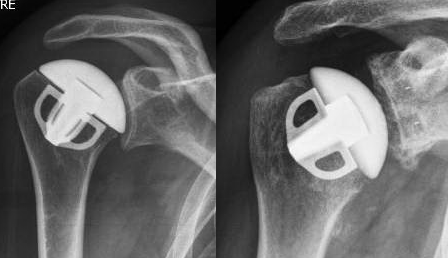

Prothèse anatomique

Ce type de prothèse est utilisée en cas d'arthrose d'épaule ou d'ostéonécrose de la tête humérale. Dans ce cas, les tendons de la coiffe des rotateurs sont compétents et l'intervention consiste à reproduire l'anatomie (cf. photo) en mettant en place une sphère métallique pour remplacer la tête humérale et une cupule en polyéthylène pour remplacer la glène de l'omoplate.

Exemple de prothèse anatomique d'épaule sans (image de gauche) ou avec (image de droite) resurfaçage de la glène